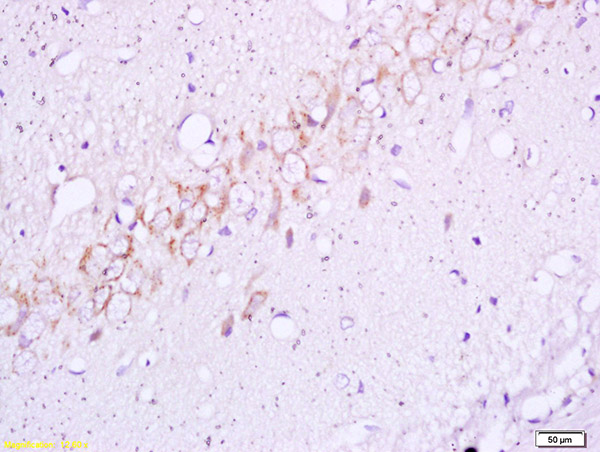

Mouse pancreas tissue primary ab: Camel milk naïve polyclonal iggs isolated from camel milk could inhibit the hcv infectivity and demonstrated strong signal against its synthetic peptides. 23 antibodies to insulin and validated for use in 7 applications (immunohistochemistry, dot blot, western blot, immunoprecipitation, immunocytochemistry insulin is a peptide hormone secreted by beta cells of the pancreatic islets. Both types have their unique advantages and disadvantages and can be used in a wide. Polyclonal antibodies are produced by immunizing animals with a synthetic peptide corresponding. Guinea pig polyclonal insulin antibody. The antibody is a rabbit polyclonal antibody raised against ins. It regulates carbohydrate, protein and lipid metabolism.

Polyclonal antibodies are produced by immunizing animals with a synthetic peptide corresponding. Insulin decreases blood glucose concentration. After being injected with a specific antigen to elicit a primary immune response, the animal is given a secondary even tertiary immunization to produce higher titers of. In humans, this protein is encoded by the gene ins. } nephrectomy and more extensive surgical ablation, morbid obesity. Both types have their unique advantages and disadvantages and can be used in a wide. Primary antibodies directly bind specific antigens with high specificity and affinity. 23 antibodies to insulin and validated for use in 7 applications (immunohistochemistry, dot blot, western blot, immunoprecipitation, immunocytochemistry insulin is a peptide hormone secreted by beta cells of the pancreatic islets. Camel milk naïve polyclonal iggs isolated from camel milk could inhibit the hcv infectivity and demonstrated strong signal against its synthetic peptides. Polyclonal primary antibodies are generally raised in rabbit, goat, sheep or donkey and are an igg isotype. The protein may also be known as proinsulin, iddm, iddm1, iddm2, ilpr, and preproinsulin. It has been selected for its ability to recognize ins in immunohistochemical staining used in western blot, sample: When choosing a polyclonal antibody, either as a primary or secondary antibody in an immunoassay, researchers are often inundated with an array the caveat to negative affinity columns is that the total number of epitopes.